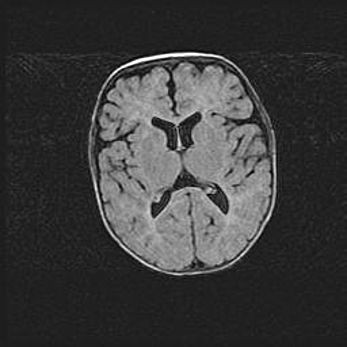

Сообщающаяся гидроцефалия. Кистозная энцефаломаляция головного мозга.

Возраст: 3 месяца 4 дня

Вес: 3100 г

Пол: женский

Окружность головы: 34 см

Срок гестации: 31 неделя

Кистозная энцефаломаляция головного мозга - одна из форм поражения головного мозга в детском возрасте. Характеризуется возникновением множественных и распространённых кист в коре, белом веществе и подкорковых образованиях головного мозга у плодов, новорождённых и детей раннего возраста. Развитие кистозной энцефаломаляции связано с внутриутробной асфиксией и гипотонией, родовой травмой, тромбозом синусов, пороками развития сосудов, инфекциями, сепсисом и другими причинами. Наиболее значимые инфекционные агенты: вирусы простого герпеса, цитомегалии, краснухи, токсоплазмы, энтеробактерии, золотистый стафилококк и другие.